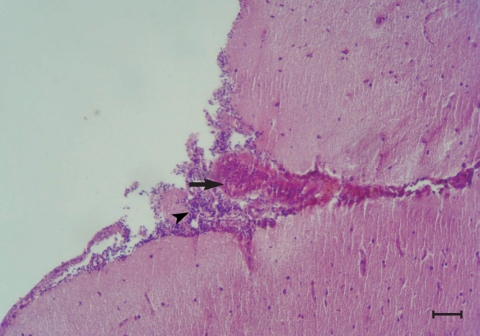

Fig. 1). Mild hemorrhages, lymphocytic infiltrations, and a few eosinophils were observed in the meninges, especially over the cerebellum (

Fig. 2). Perivascular infiltration was seen around some of the vessels in the cerebral parenchyma in most of the infected chickens. Mild focal infiltration of lymphocytes was present between cardiac muscle fibers of the infected chickens. No lesions were seen in other tissues of the infected chickens. No abnormality was observed at gross and histological levels in the liver, lungs, kidneys, heart, brain, and other tissues examined of uninfected control chickens.

Fig. 2Congestion (arrow) and infiltration of lymphocytes (arrow head) in the meninges of the brain from a chicken infected with 1,000 T. cati eggs on day 240 PI. H-E stain. Scale bar = 175 µm).